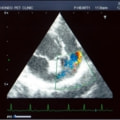

症例6:【ACVIM StageD ビーグル 10歳 去勢雄】

C:超音波 僧帽弁逆流のカラードップラー画像

D:La/Ao比の重度拡大あり

左側胸壁心尖部領域を最強点とするLevine 5/6の収縮期性心雑音が聴取された。安静時にも咳が認められる。胸部レントゲン検査において重度の心拡大が及び肺水腫が認められた。超音波検査では、重度の僧帽弁閉鎖不全、三尖弁閉鎖不全が認められた。三尖弁逆流速度から肺高血圧症が示唆された。ACE阻害薬、ピモベンダン、硝酸イソソルビド徐放剤、ベラプロストナトリウム、利尿剤としてフロセミド及びスピロノラクトンを用いて治療を行っている。